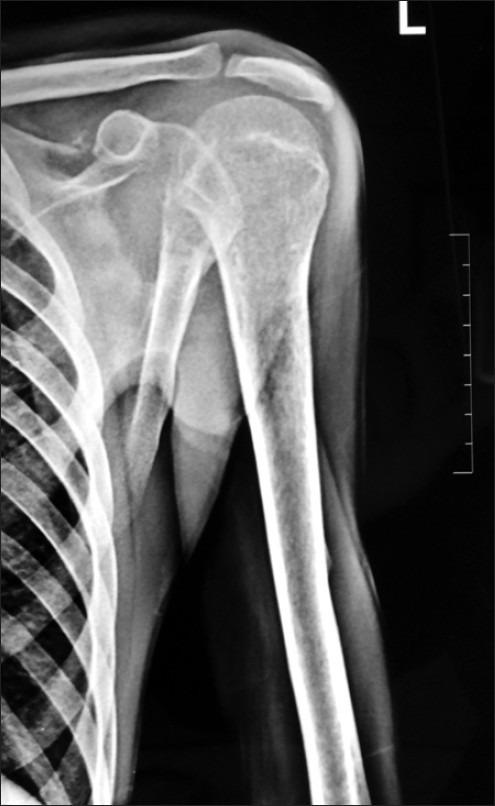

Metastasis to left scapula with unknown primary: Approach to pathological diagnosis.

South Asian J Cancer. 2013 Jan;2(1):2. doi: 10.4103/2278-330X.105856.